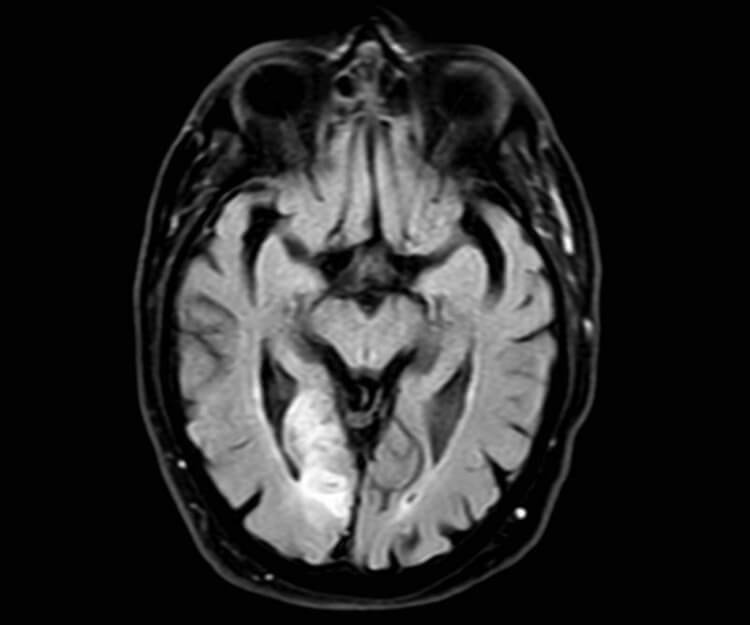

Figure 1: MRI head. 52x16mm restricted diffusion lesion in the right

occipital lobe region with associated high T2 signal in keeping with an acute infarct.

Small 4mm focus of restricted diffusion in the left occipital lobe may represent an acute infarct.